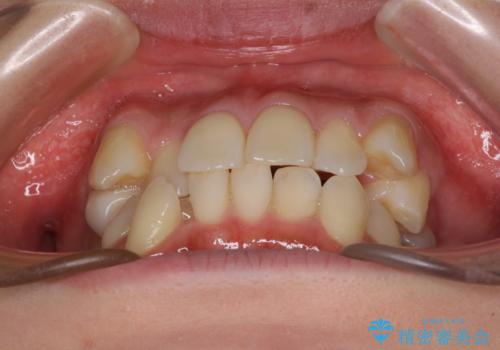

- デコボコの歯列で歯磨きがしにくいことを気にして来院された患者様です。

右側の上下は歯が重なり合って、内側に移動してしまうほどであり、それに伴って正中の位置が右側にずれている状態でした。

上下左右の第一小臼歯4本を抜歯して行うことになりますが、それだけでは咬み合わせの改善や正中位置の改善が困難であると判断されたため、アンカースクリューを用いた補助装置を併用することで、スムーズかつより良い仕上がりを目指すこととしました。